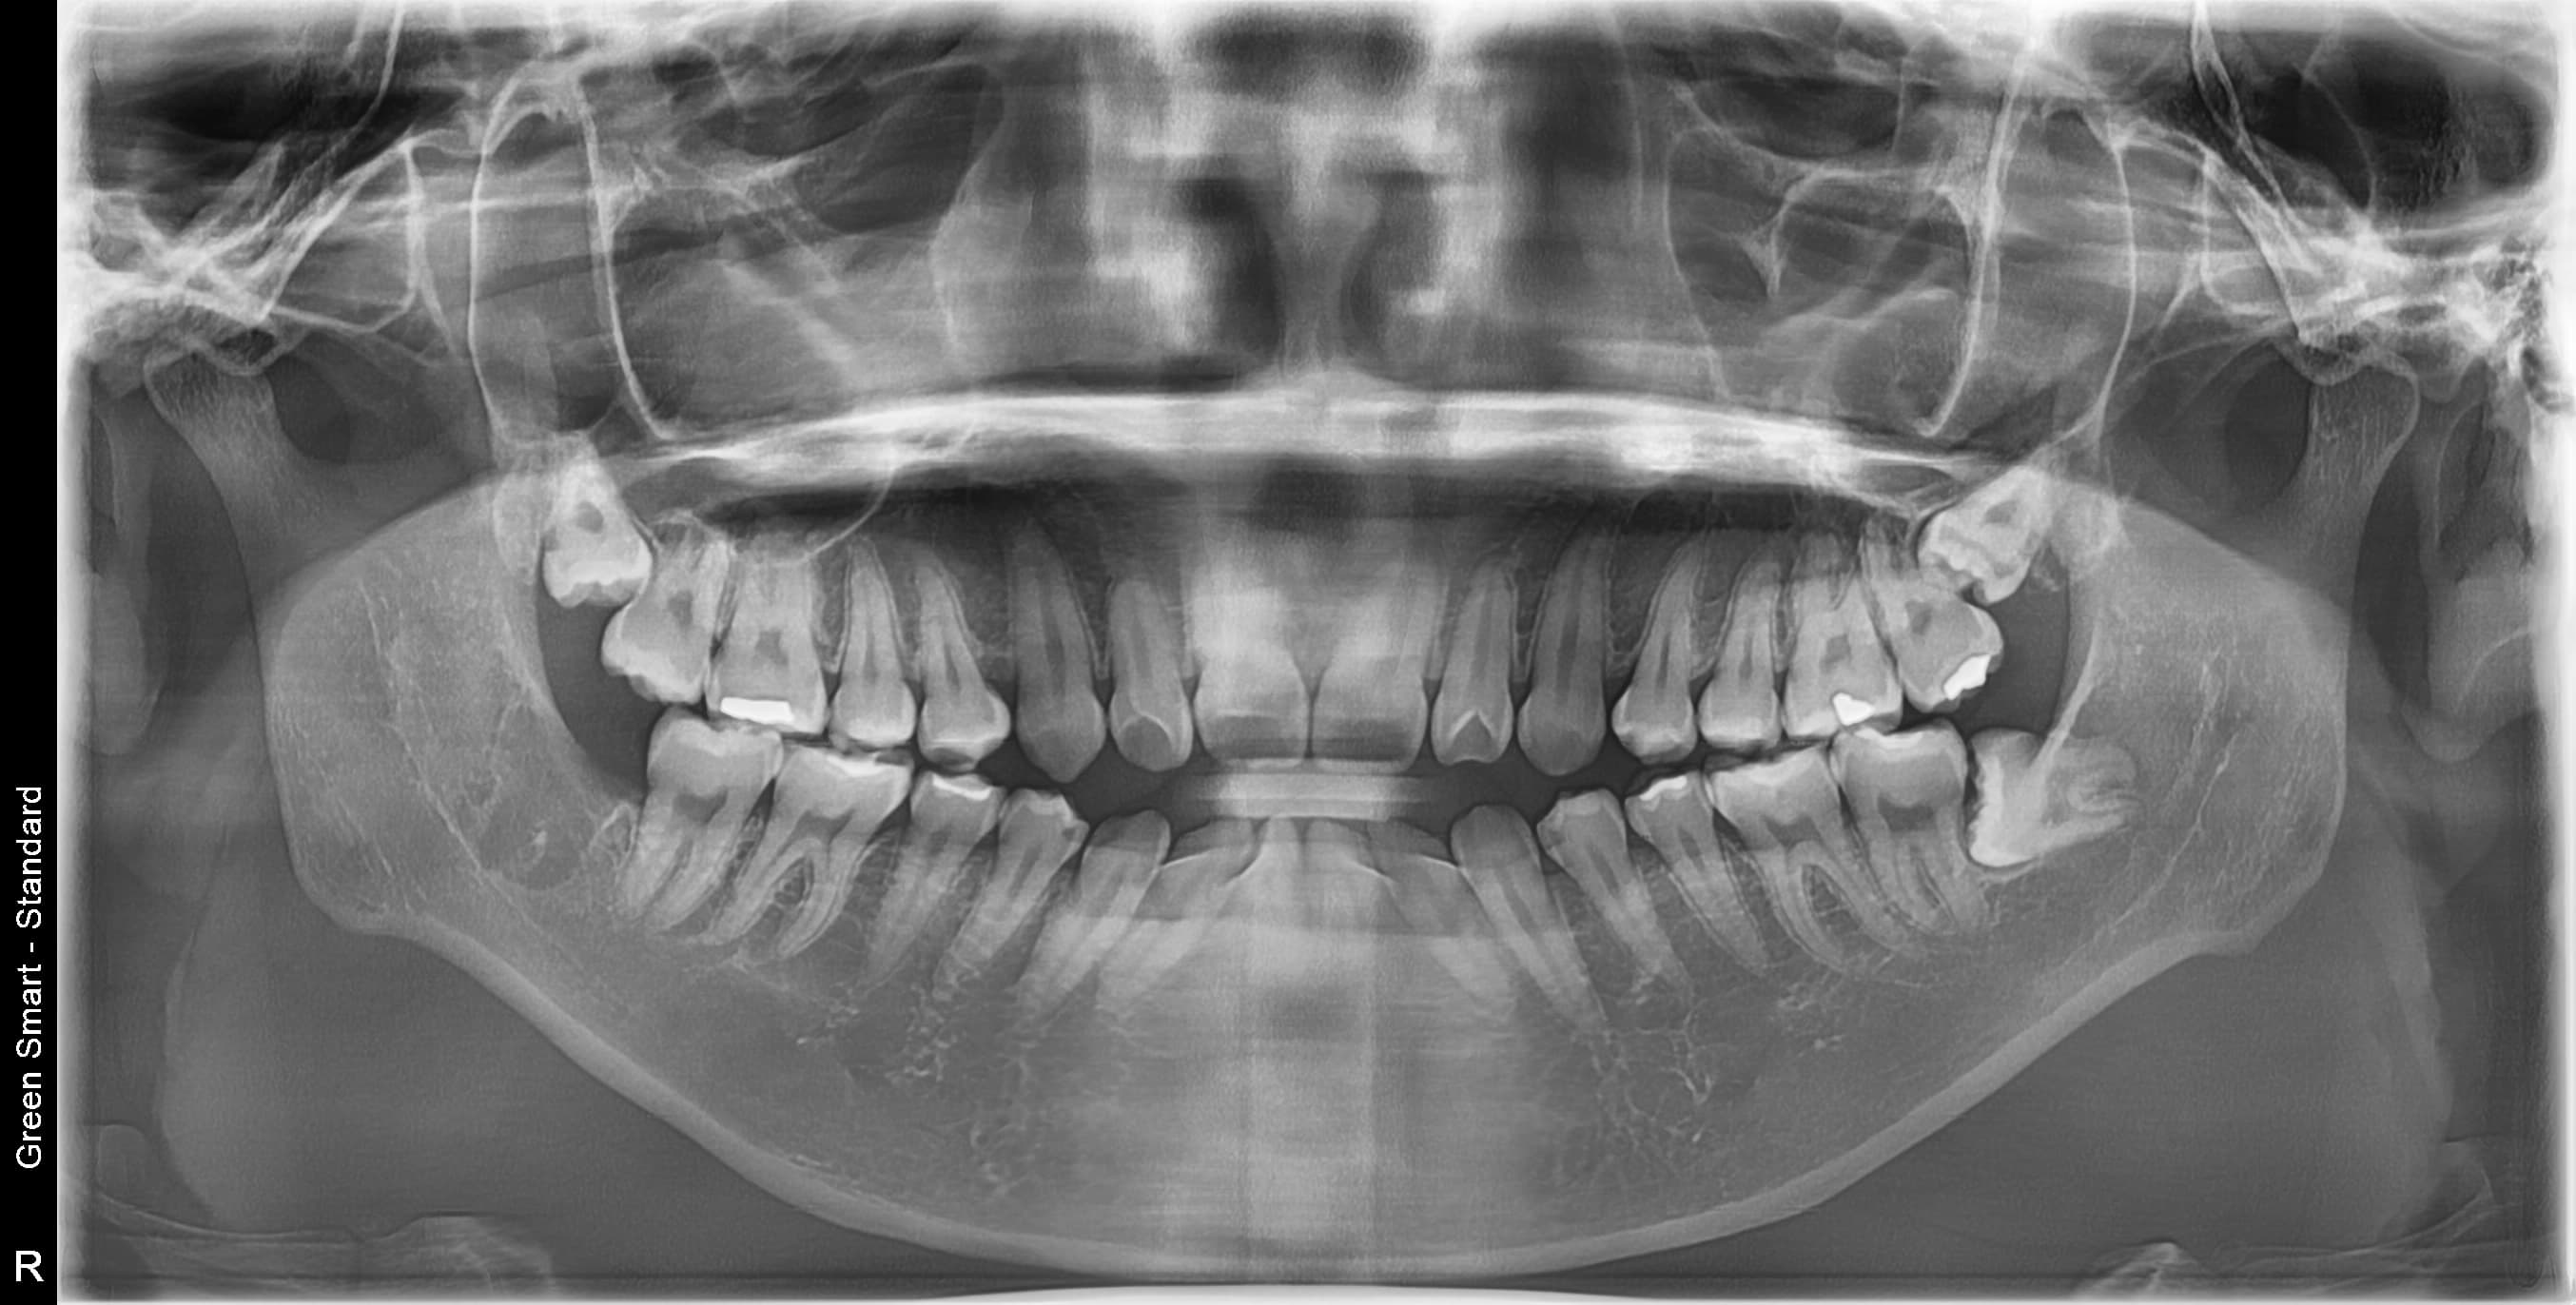

즉시 처치 필요

수평매복 사랑니

앞 치아를 밀어 치열 불균형과 충치를 유발합니다

복잡한 매복 사랑니 — 잇몸 속 깊이 묻혀있어도 OK

신경 근접 사랑니 — 신경 손상 걱정 없는 안전한 발치

수평 매복 사랑니 — 옆으로 누워있는 어려운 케이스도 가능

왜 지금 발치해야 할까요?

사랑니 방치 시 발생하는 문제

급성 염증

심한 통증과 얼굴 부종

인접 치아 충치

옆 치아까지 손상

턱관절 장애

만성 두통과 턱 통증

치열 불균형

교정 치료 필요